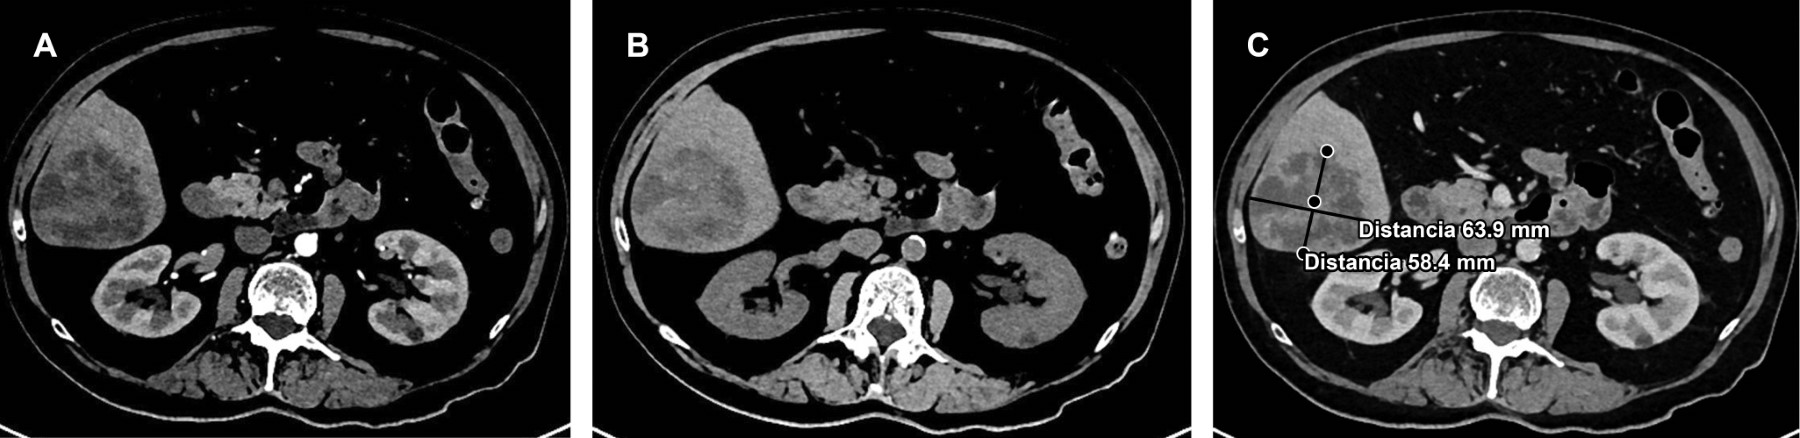

En la tomografía computarizada es característica la lesión única, sólida o multiloculada, de pared delgada, que involucra habitualmente un solo lóbulo hepático (Figura 2).3

Figura 2